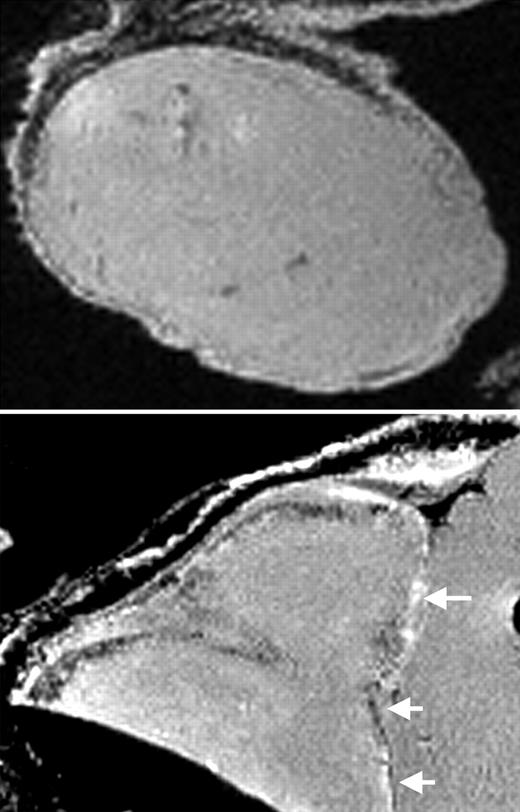

Writing in this issue of Blood, Arbab and colleagues strongly suggest an affirmative answer to the latter question in their use of a combination of FDA-approved agents to label several human and murine cell types. The authors use the commonly used transfection agent protamine sulfate to modify a commercially available suspension of dextran-coated SPIOs known as ferumoxides. Protamine sulfate is FDA approved for the treatment of heparin overdoses, while ferumoxides have been FDA approved for use as an MR contrast agent in the diagnosis of liver cancer for more than 7 years in the form of Feridex IV (Berlex Laboratories, Wayne, NJ). The article establishes that the combination of these agents results in an effective preparation of magnetically labeled cells. In the article, the authors initially define ferumoxide–protamine sulfate ratios that provide optimal relaxation properties for contrast enhancement, and proceed to demonstrate that this combination permits extremely high labeling efficiency as well as minimal short- and long-term effects on cellular toxicity, proliferation, and differentiation in the examined cell types. In so doing, this research identifies a promising magnetic cell-labeling strategy that is appropriate for potential clinical development and delineates a paradigm for the evaluation of such strategies prior to clinical implementation. This group has pioneered the use of transfection agents in combination with SPIOs for cell labeling and MR-based cell tracking.4 The authors' progress in this area affords an example of the systematic development of bench research for bedside application. The work of Arbab et al represents an important step in this effort, suggesting the prospective design of future clinical trials.FIG1

MRI of labeled CD34+ cells in tumors. See the complete figure in the article beginning on page 1217.

MRI of labeled CD34+ cells in tumors. See the complete figure in the article beginning on page 1217.